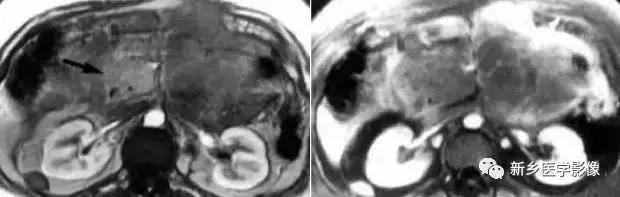

2.影像学诊断:CT 、M RI 上, 本病表现为胰腺边界清楚的大肿块, 囊实相间, 实性部分主要位于病变周边,有强化;囊性部分主要位于病灶中心区域, 囊变区密度较高, CT 值40 ~50Hu 。30 %的患者病变周边可见钙化。由于病变内常有出血,T1W I 上可见不均匀高信号, T 2WI 上见不均匀低信号 。M RCP 或E RCP 示胰管受压、移位或中断。